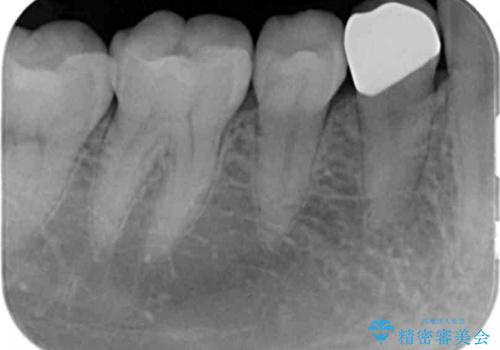

- 銀歯が目立つから白くしたいとのことで来院されました。

当初は元の詰め物と同じインレータイプでの修復予定でしたが、残った歯の厚みが薄く、今後の破折リスクを考慮しクラウンタイプでの修復処置となりました。

- 右下4 仮歯+ジルコニアクラウン 11000円+110000円費用は治療当時の料金となります

残った歯が薄い状態で保存するとその後の破折リスクが高くなります。

予防的に歯を削りクラウンにすることで治療後の破折リスクを減らすことができます。